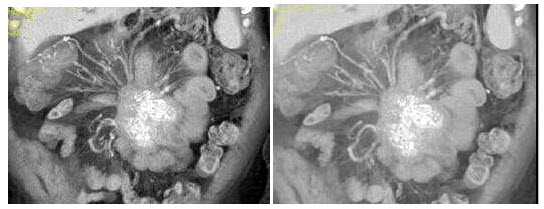

2、单项选择题

根据所提供的图像,最可能的诊断是()

A.转移癌

B.肝癌

C.局灶性结节增生

D.血管瘤

E.肝脓肿